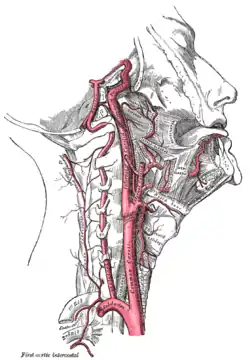

Diagram showing the origins of the main branches of the carotid arteries. The internal carotid and vertebral arteries. Right side. (Superior thyroid visible at center.)

The internal carotid and vertebral arteries. Right side. (Superior thyroid visible at center.) The thyroid gland and its relations.